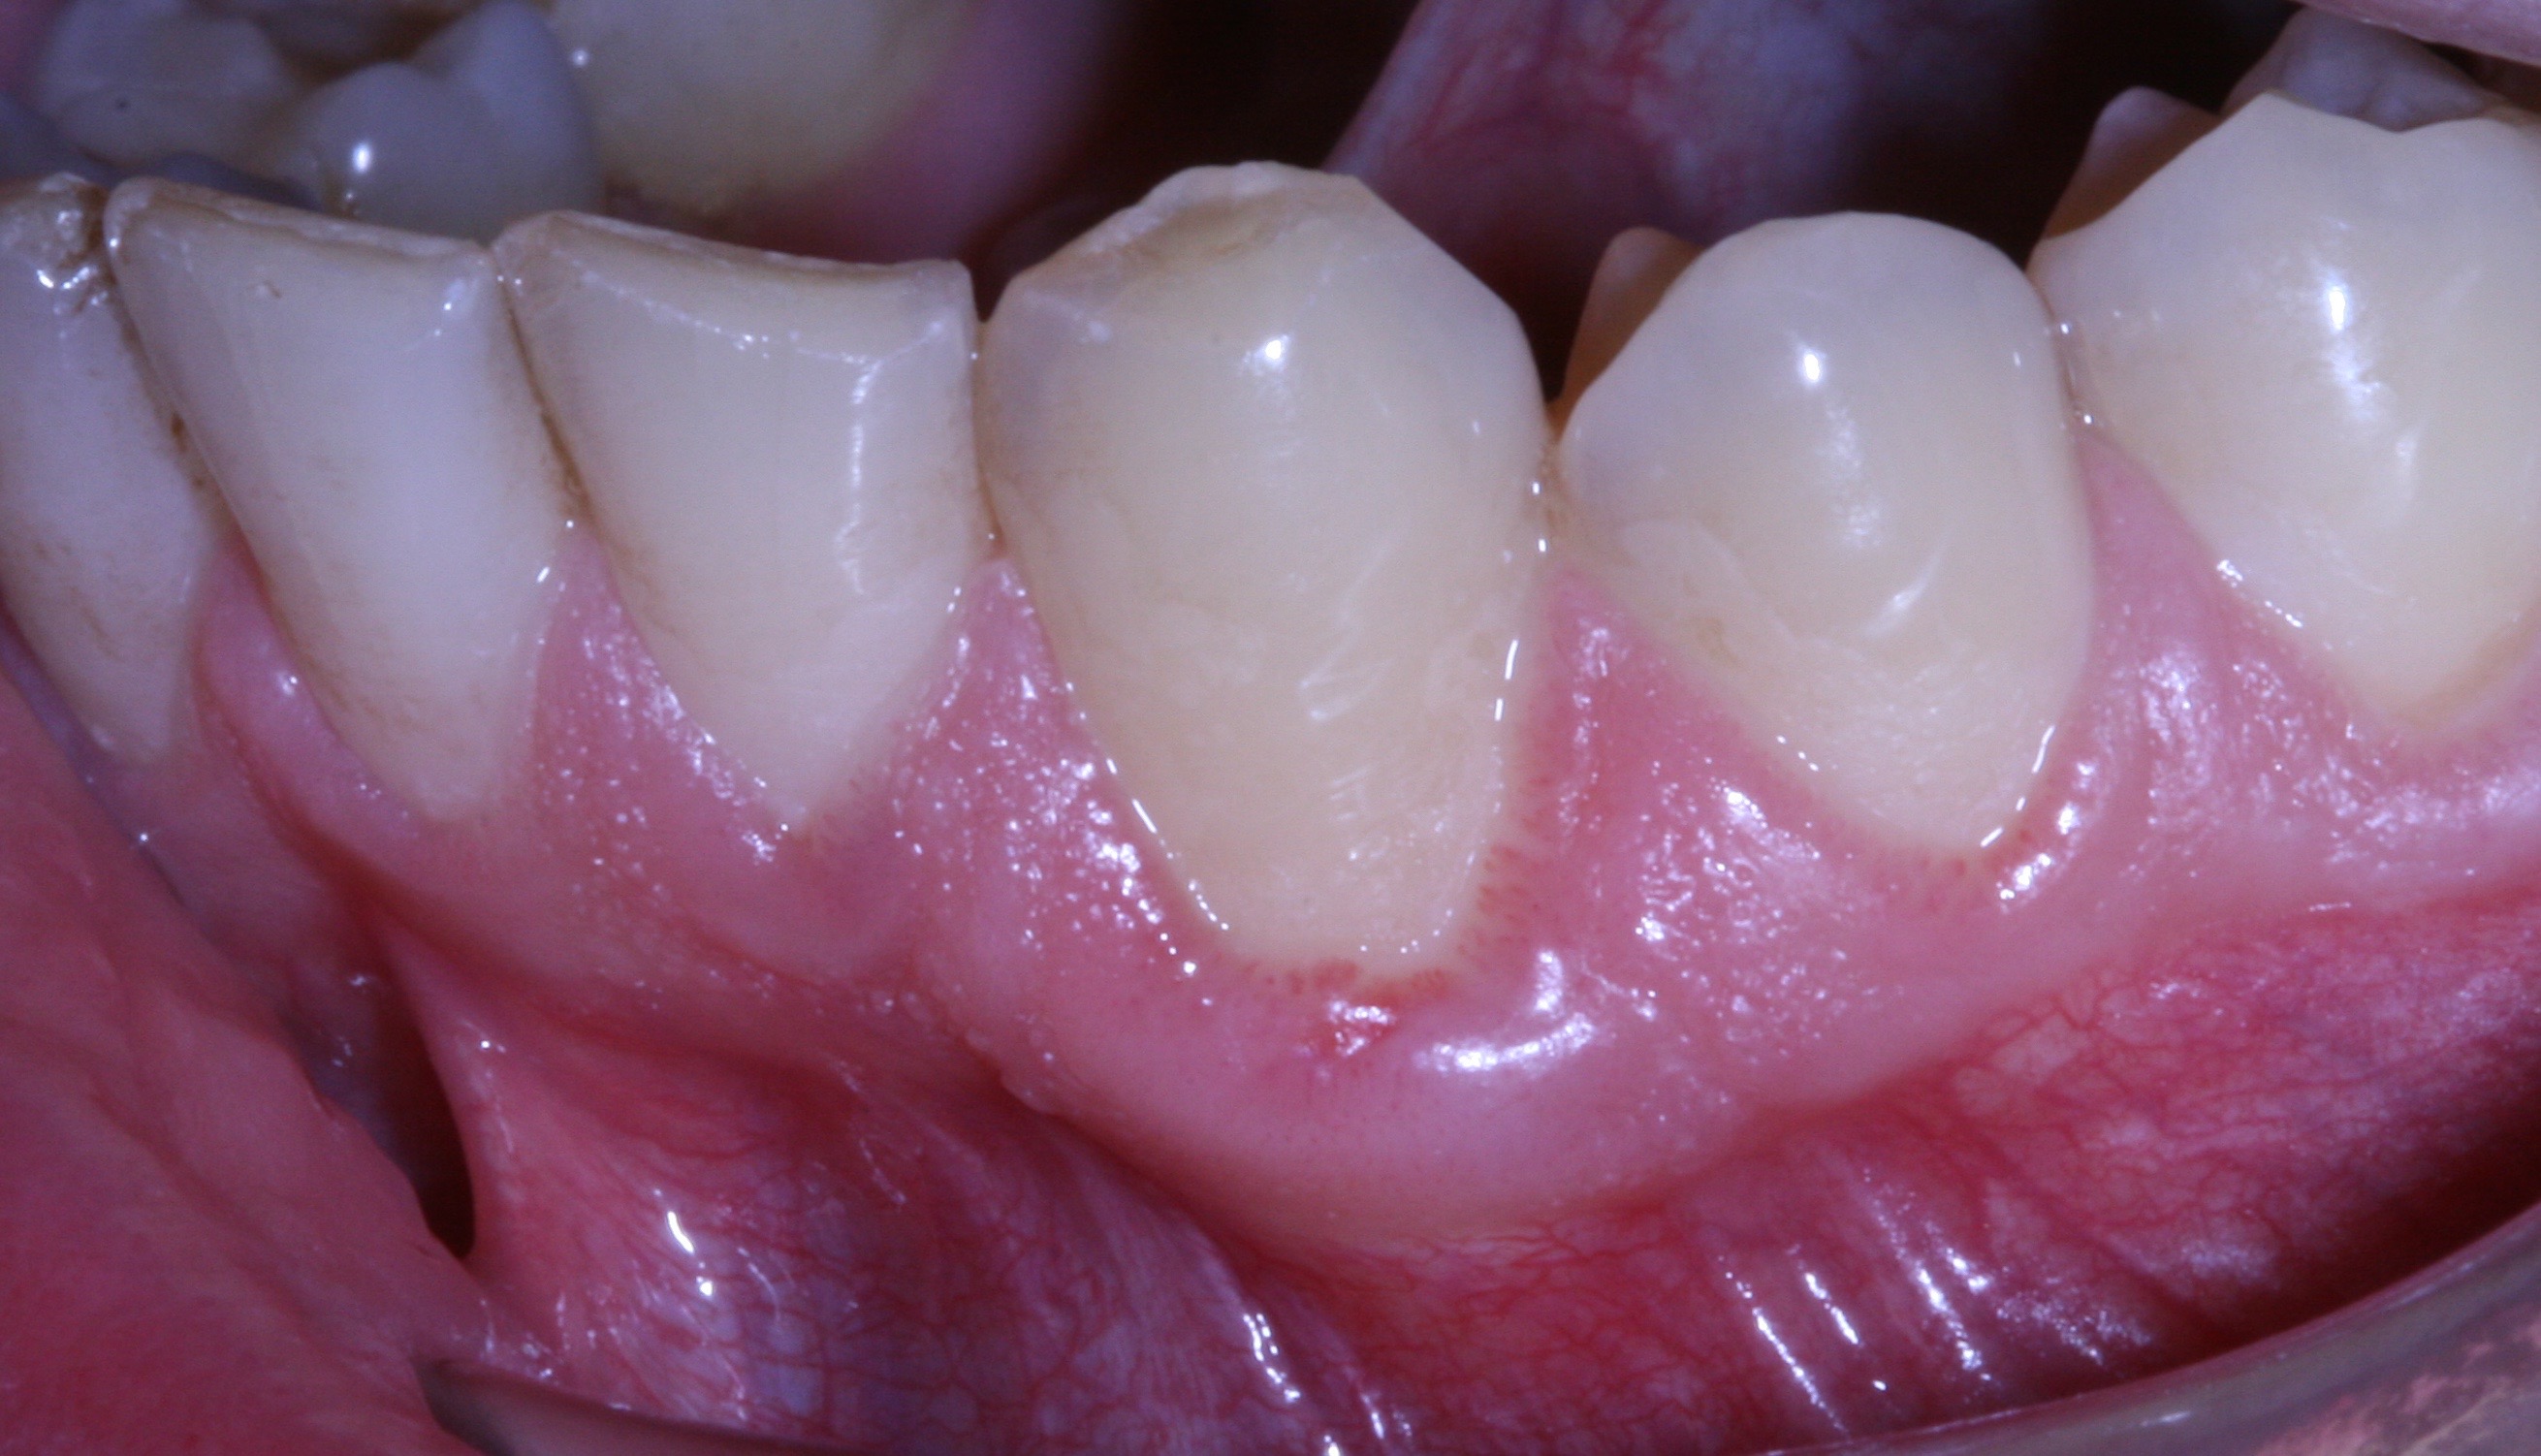

Lesione iniziale